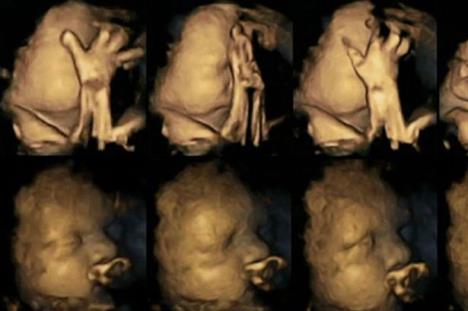

Doktorka Nađa Rajsland je 4D skenerom snimala hiljade pokreta fetusa u materici. Pratila je 20 trudnica, od čega su njih 4 pušile preko 14 cigareta dnevno

Istraživanje je napravljeno kako bi pomoglo mamama koje se muče da ostave cigarete. Doktorka Nađa Rajsland je 4D skenerom snimala hiljade pokreta fetusa u materici. Pratila je 20 trudnica, od čega su njih 4 pušile preko 14 cigareta dnevno.

Ona je nerođenu decu posmatrala u trenucima kad su bila stara 24, 28, 32 i 36 nedelja. Primetila je da su deca u stomacima trudnica koje su pušači mnogo češće pomerala usta i pipala se nego ona koja su bila u stomacima trudnica nepušača.

Fetusi u toku trudnoće dodiruju sebe sve manje i manje, do trenutka porođaja. Pogledajte kako bebe reaguju na ovu lošu naviku njihovih mama: